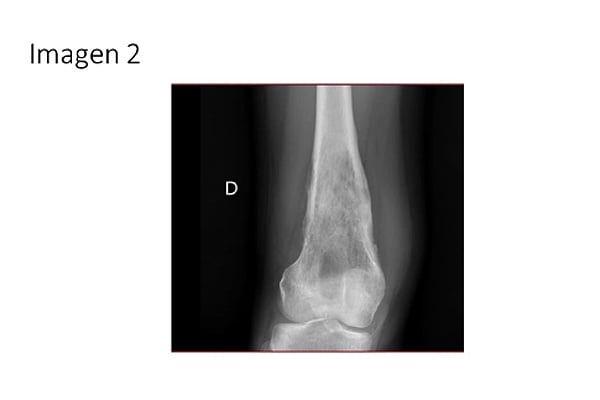

2. ¿Cuál de los siguientes hallazgos radiográficos es más útil para diferenciar osteosarcoma de otras causas de dolor crónico de rodilla en adolescentes (IMAGEN 2)?: